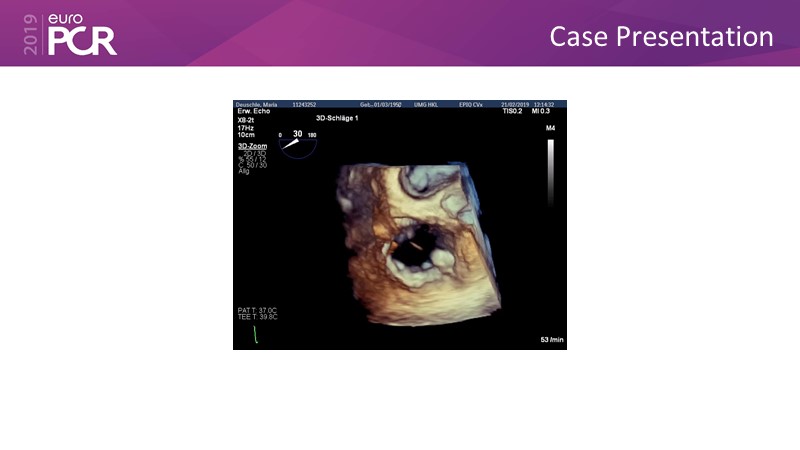

Addressing tricuspid regurgitation with annular reduction: the Cardioband tricuspid system

Consult this session to understand how patients with tricuspid regurgitation and annular dilatation can benefit from Cardioband system...

- To understand how patients with tricuspid regurgitation and annular dilatation can benefit from Cardioband system

- To learn how to perform a good echo workup for Cardioband tricuspid system